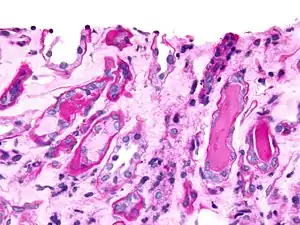

Epithelial cell casts

This cast is formed by inclusion or adhesion of desquamated epithelial cells of the tubule lining. Cells can adhere in random order or in sheets and are distinguished by large, round nuclei and a lower amount of cytoplasm. These can be seen in acute tubular necrosis and toxic ingestion, such as from mercury, diethylene glycol, or salicylate. In each case, clumps or sheets of cells may slough off simultaneously, depending of the focality of injury. Cytomegalovirus and viral hepatitis are organisms that can cause epithelial cell death as well.